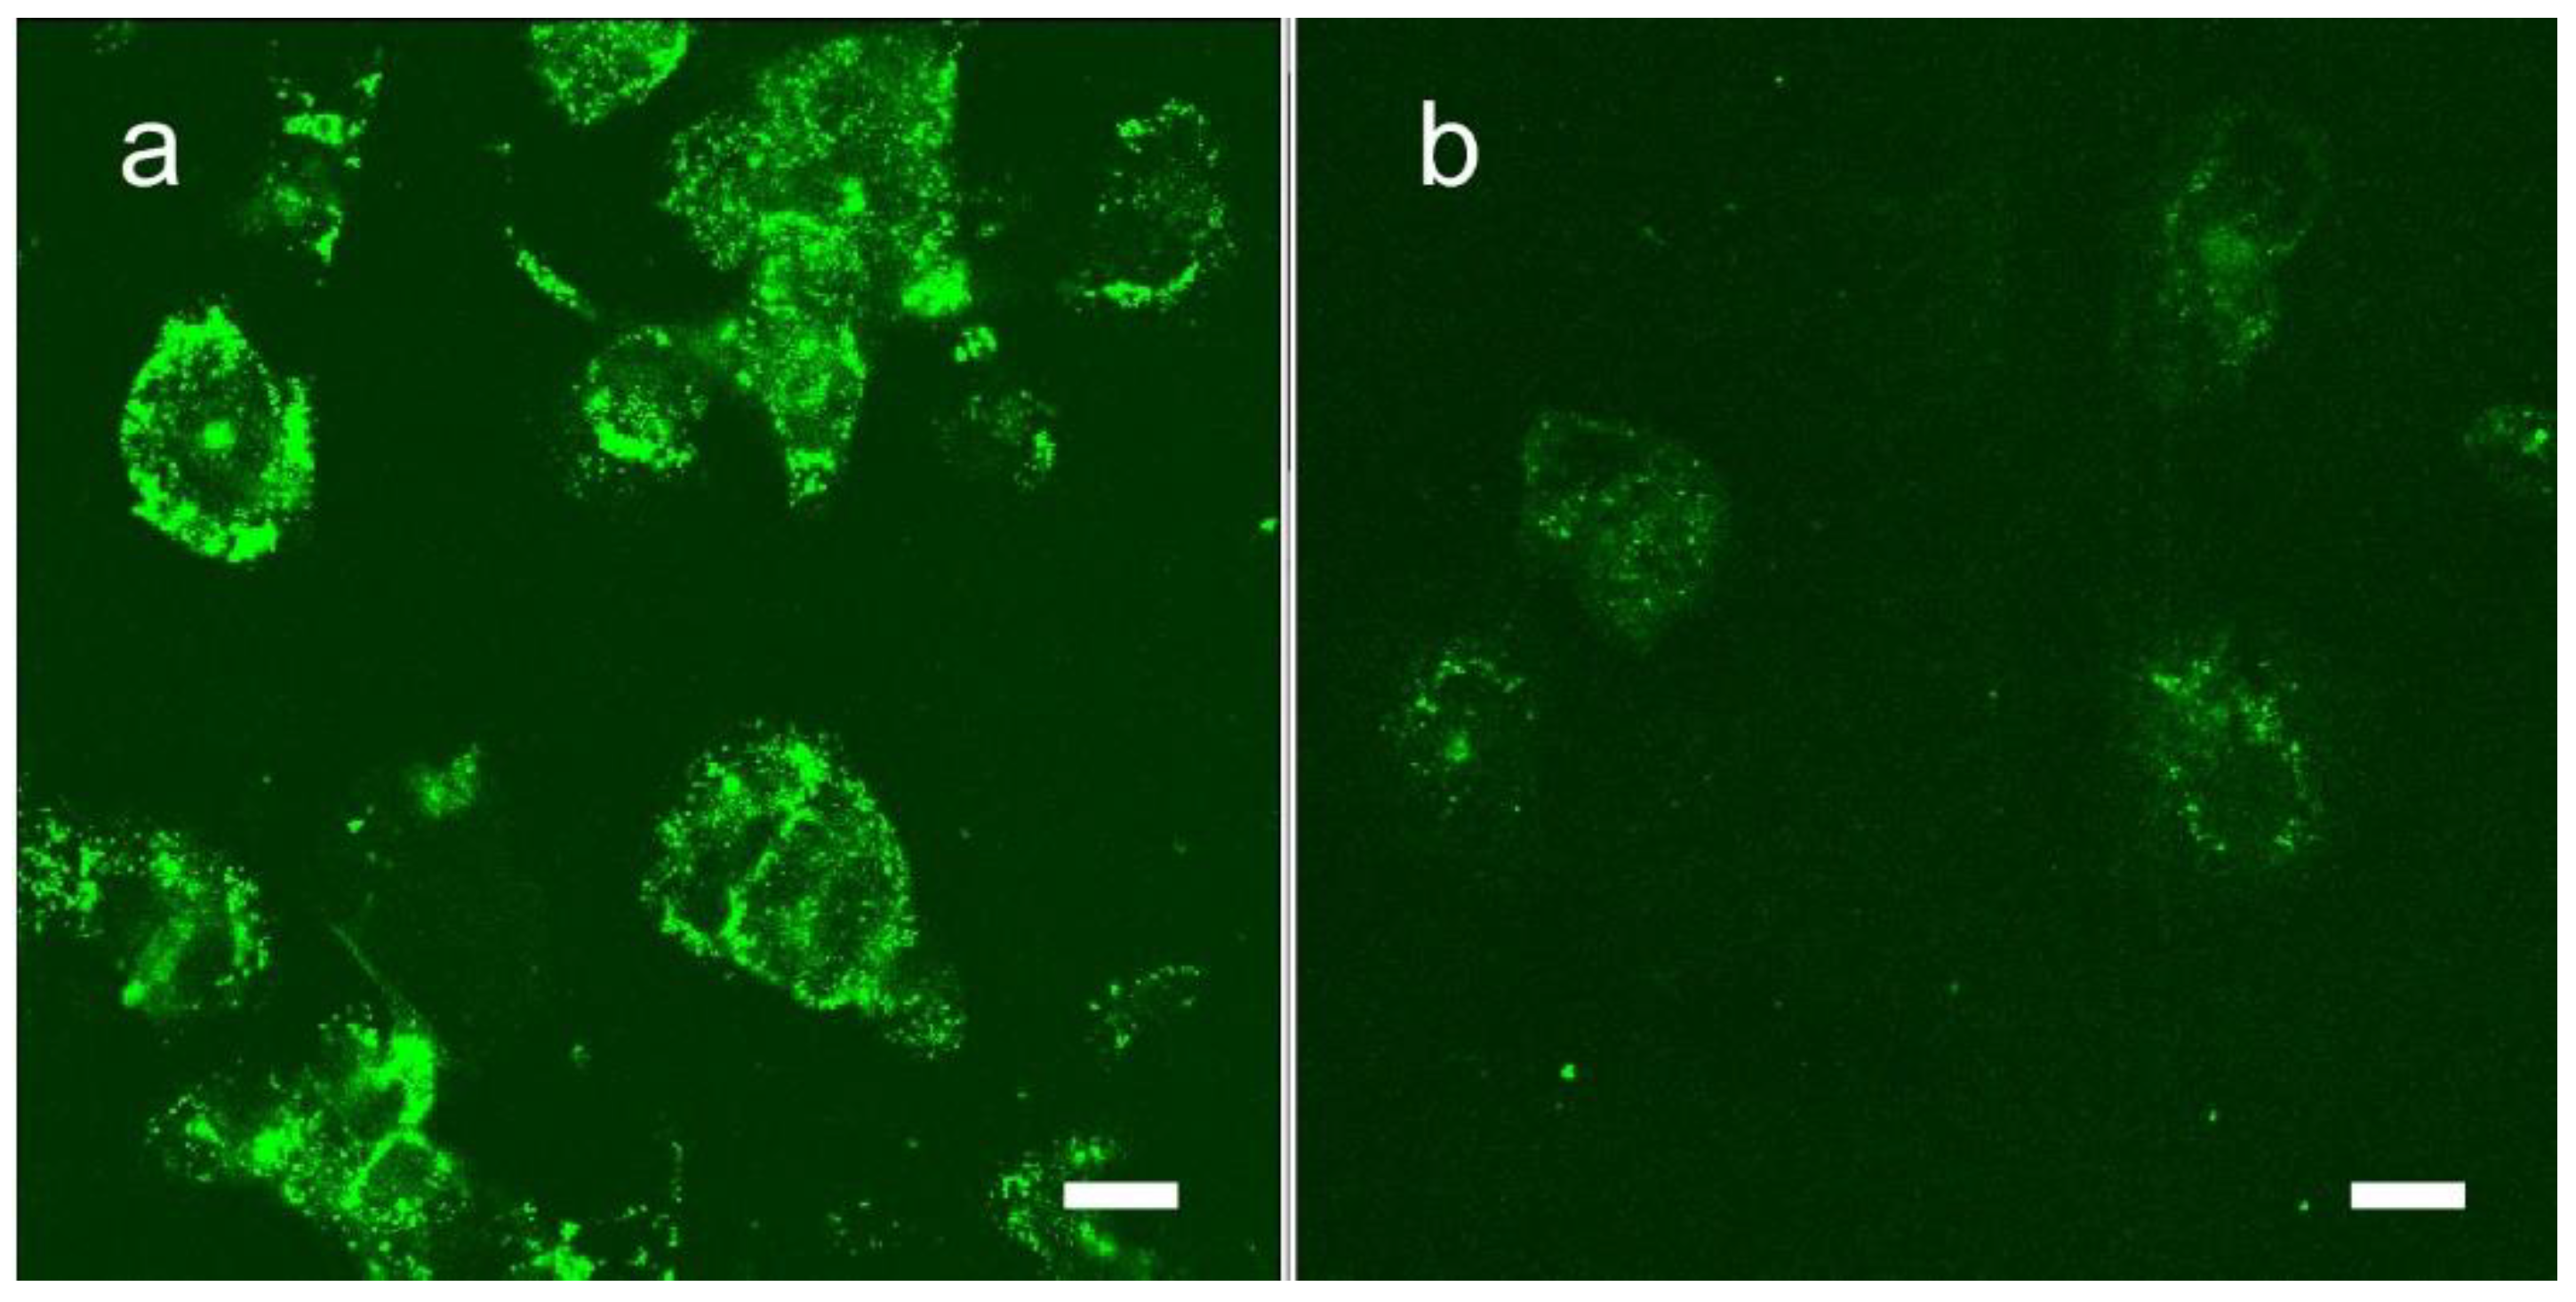

1.7. Iodine Nanoparticle Targeting

1.8. Iodine-Enhanced Radiotherapy of Brain Metastases

1.9. Iodine Nanoparticle Targeting to Brain Metastases